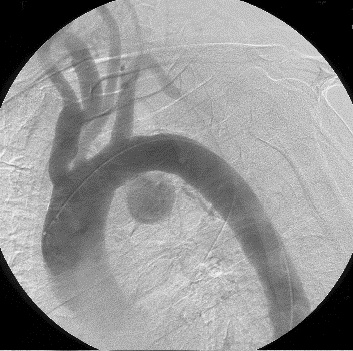

4)大動脈瘤に対するステントグラフト治療

大動脈瘤に対する手術は、以前は開胸もしくは開腹による人工血管置換術でした。近年はカテーテル治療(ステントグラフト挿入術)が積極的に行われており、手術の低侵襲化と成績向上に寄与しています。ただし、すべての患者さんにこの方法が適しているわけではありませんのでご注意下さい。

ステントグラグト挿入術:レントゲン透視下に実施

胸部大動脈瘤のステントグラフト治療